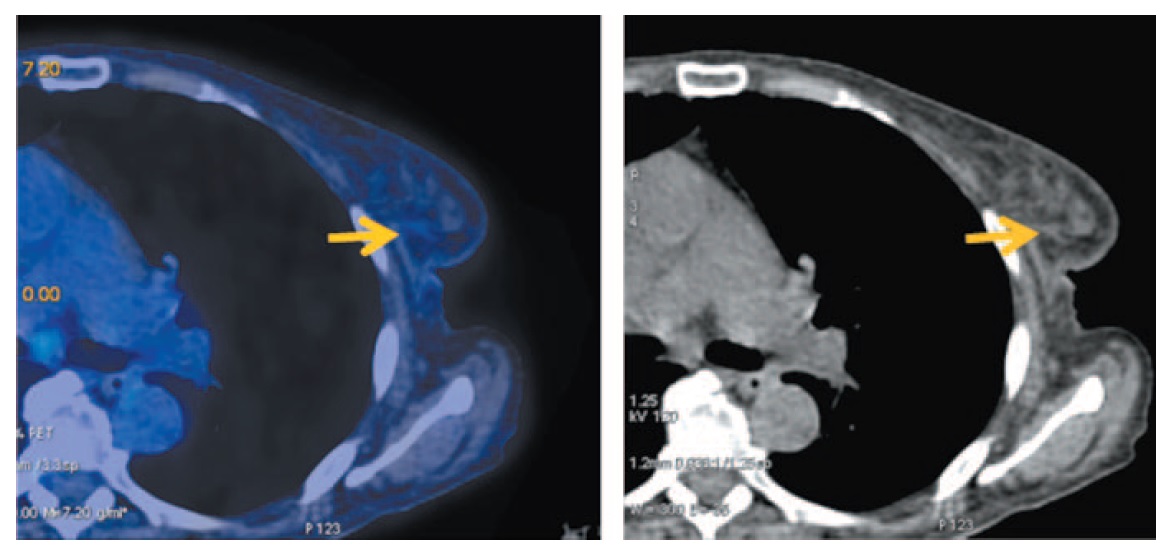

После 6 циклов указанного лечения с целью оценки эффекта проводимой терапии выполнена ПЭТ/КТ с 18-ФДГ. При этом отмечаются незначительное уменьшение размеров щитовидной железы и снижение ее метаболической активности в 1,9 раза (рис. 4).

Рис. 4. Больная Б., 72 года. Состояние после 6 циклов таргетной и гормонотерапии. На MIP и аксиальных ПЭТ/КТ проекциях сохраняется диффузное умеренное увеличение размеров щитовидной железы до 6×20 мм правой доли и 11×22 мм левой доли. Фиксация РФП снизилась до SUVmax 5,74, ранее 10,90. / Fig. 4. A 72-year-old woman. The condition of the patient after 6 cycles of targeted and hormone therapy. Axial MIP and PET/CT images show the persisted moderate diffuse enlargement of right and left lobes of the thyroid gland measuring 6×20 mm and 11×22, respectively. RFP uptake is decreased to SUVmax 5.74, previously 10.90.

Опухоль в левой молочной железе не определяется, т.е. получена полная регрессия (рис. 5).

Рис. 5. Больная Б., 72 года. Состояние после 6 циклов таргетной и гормонотерапии. На аксиальных ПЭТ/КТ проекциях в верхне-наружном квадранте левой молочной железы узловое образование не дифференцируется, очагов фиксации РФП не выявлено. / Fig. 5. A 72-year-old woman. The condition of the patient after 6 cycles of targeted and hormone therapy. Axial MIP and PET/CT images show that lump in the upper outer quadrant of left breast is not differentiated and without focal increased RFP uptake.

Ранее увеличенные медиастинальные лимфатические узлы всех групп уменьшились в размерах в 1,9 раза, равно как и фиксация 18-ФДГ снизилась до фоновой. Кроме того, в костях скелета отмечается нарастание остесклеротической плотности на фоне вторичных очагов (рис. 6).

Рис. 6. Больная Б., 72 лет. Состояние после 6 циклов таргетной и гормонотерапии. На аксиальных и сагиттальных ПЭТ/КТ проекциях медиастинальные лимфоузлы (паратрахеальные верхней и нижней группы, бронхопульмональные с двух сторон, бифуркационные) сократились до 8 мм, ранее 15 мм. Фиксация РФП снизилась до фоновой, SUVmax 3,64, ранее 5,07. В костях скелета отмечается нарастание остеосклеротической плотности на фоне вторичных очагов. Сохраняется очаговый гиперметаболизм в единичных очагах ФДГ SUVmax 7,77. / Fig. 6. A 72-year-old woman. The condition of the patient after 6 cycles of targeted and hormone therapy. Axial and sagittal PET/CT images show that mediastinal lymph nodes (upper and lower paratracheal, bronchopulmonary on both sides, bifurcation groups of lymph nodes) have become 8 mm, previously 15 mm. The RFP uptake is decreased to baseline, SUVmax 3.64, previously 5.07. In the bones of the skeleton there is an increase in osteosclerotic density against the background of secondary transformation (metastases). The focal hypermetabolism is still detected in the single focal areas of FDG uptake SUVmax 7.77.